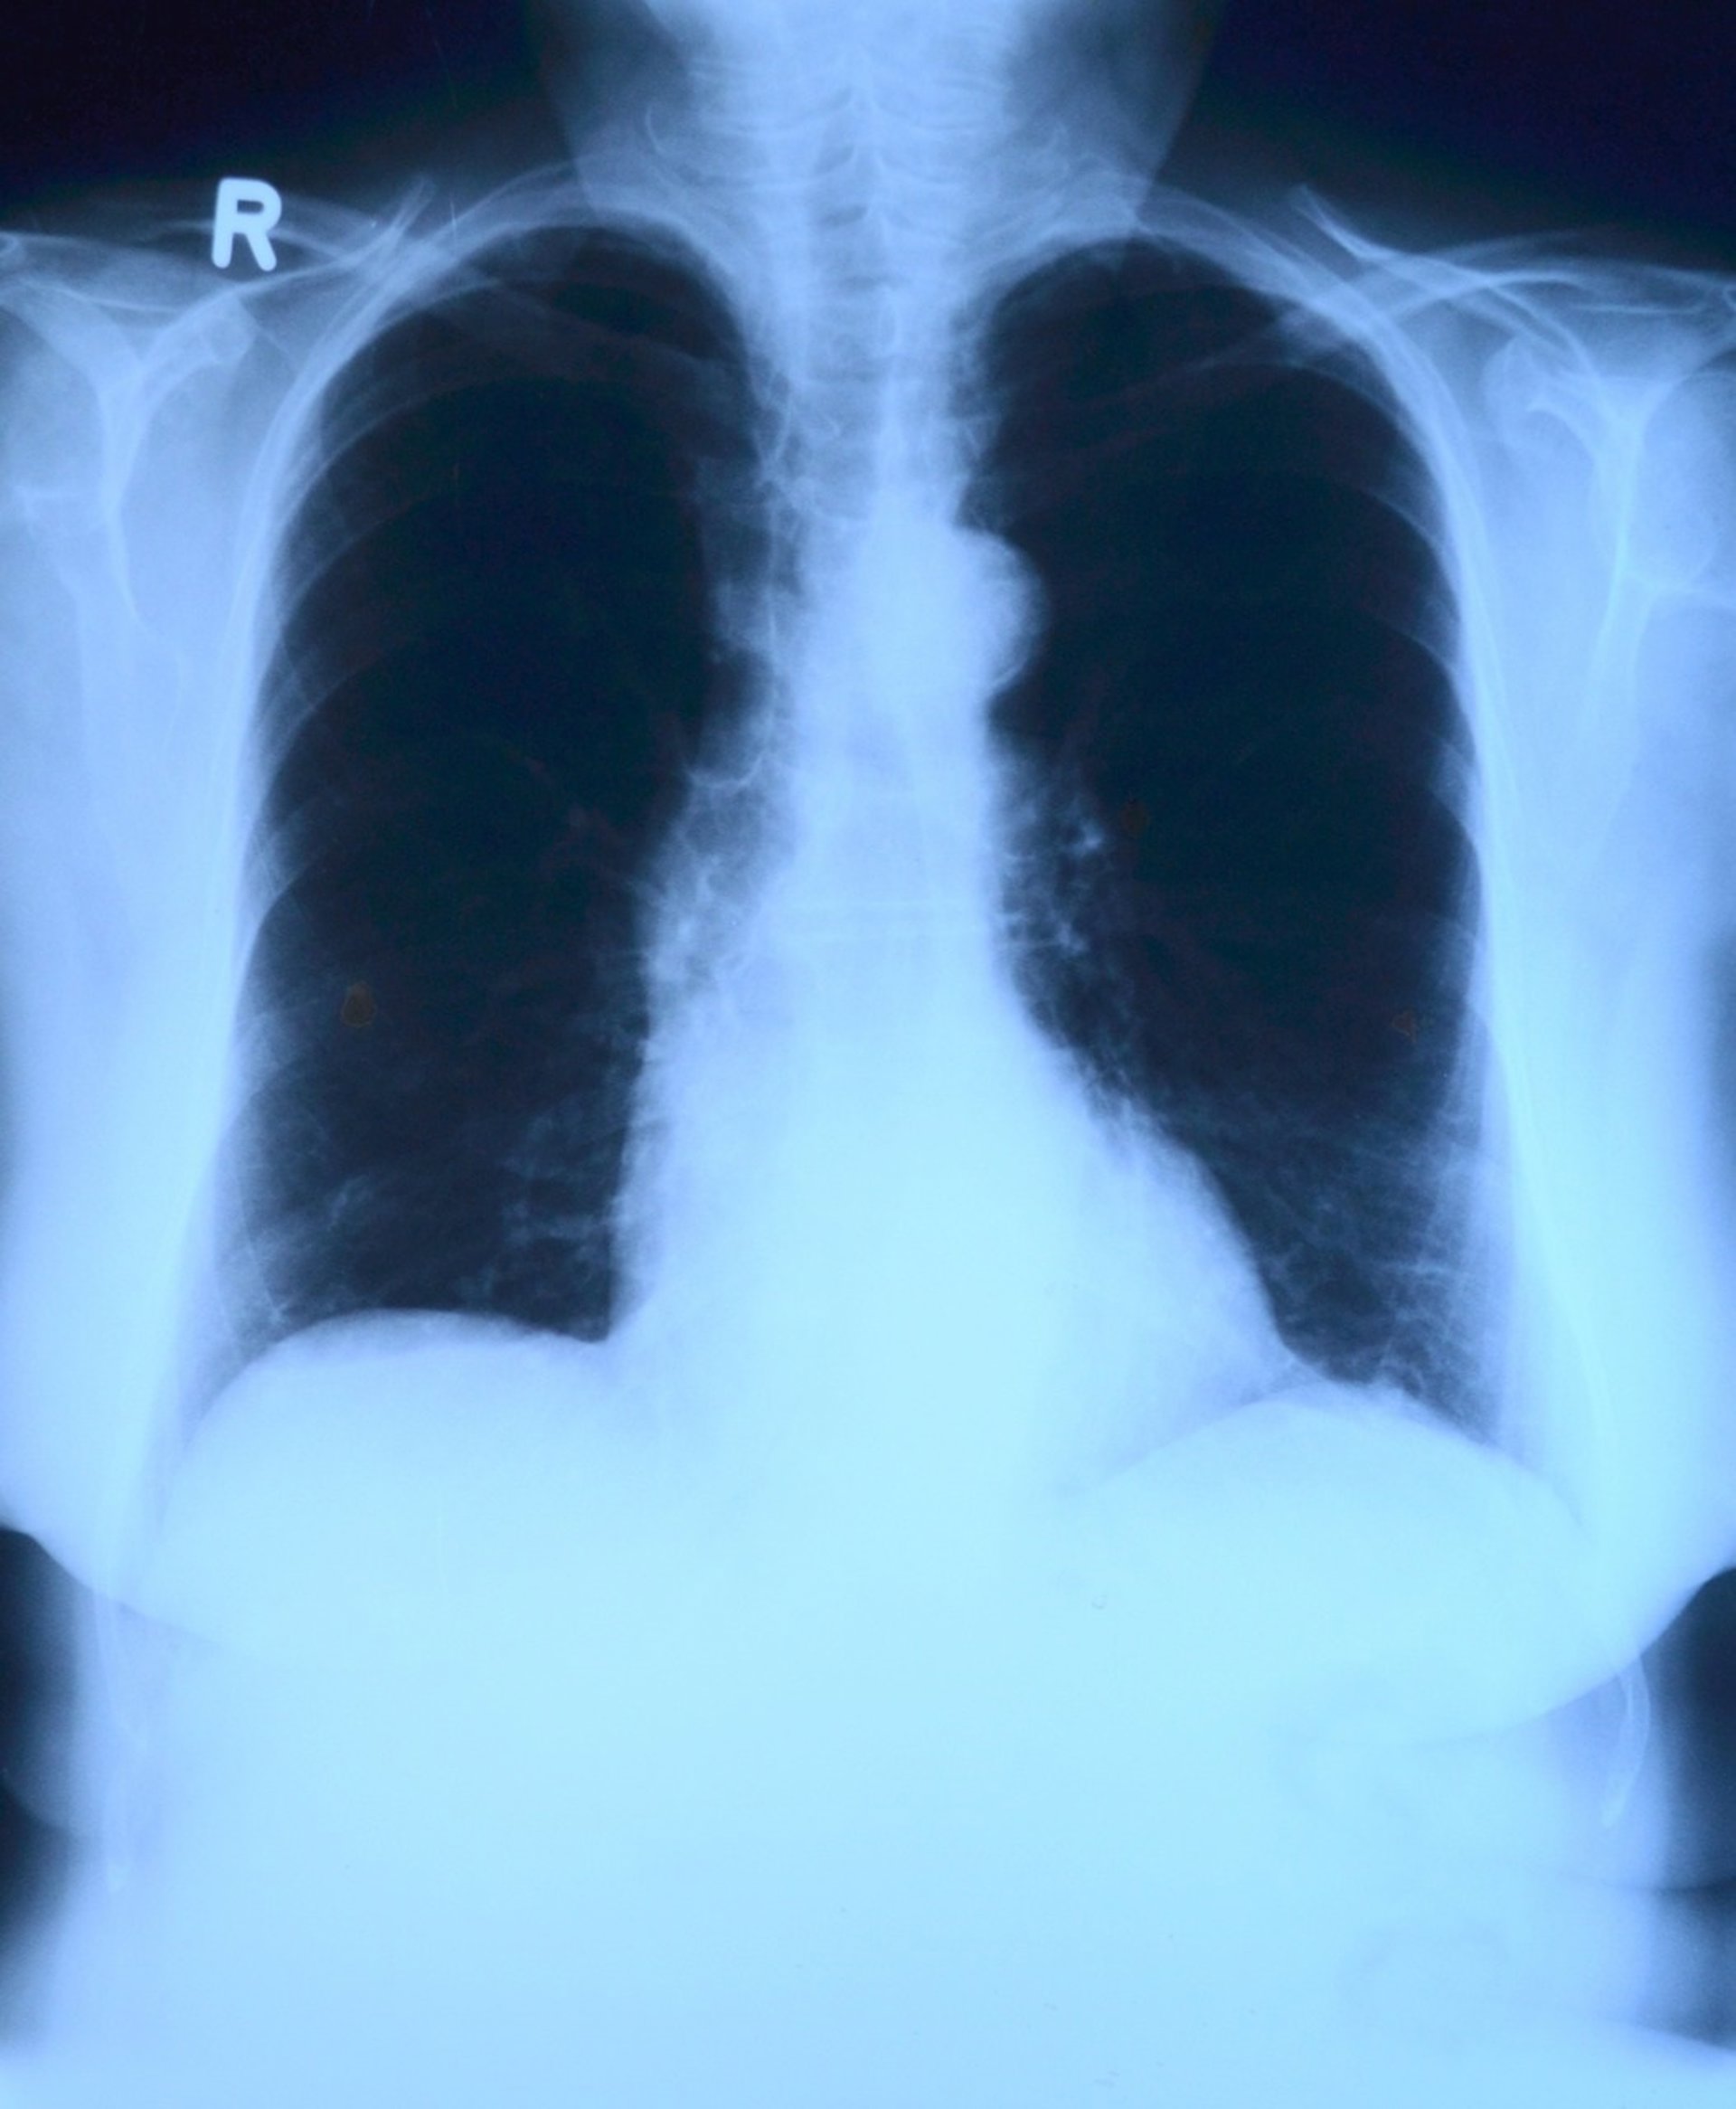

Solo un 10% de los pulmones donados sirven para trasplantes

La mayoría de los pulmones donados no sirven para trasplantes

Solo un 10 por ciento de los pulmones donados sirven para trasplantes, de forma que en 2014 solo se trasplantaron 262 pulmones de un total de 1.682 donantes multiorgánicos, según datos de la Organización Nacional de Trasplantes (ONT).